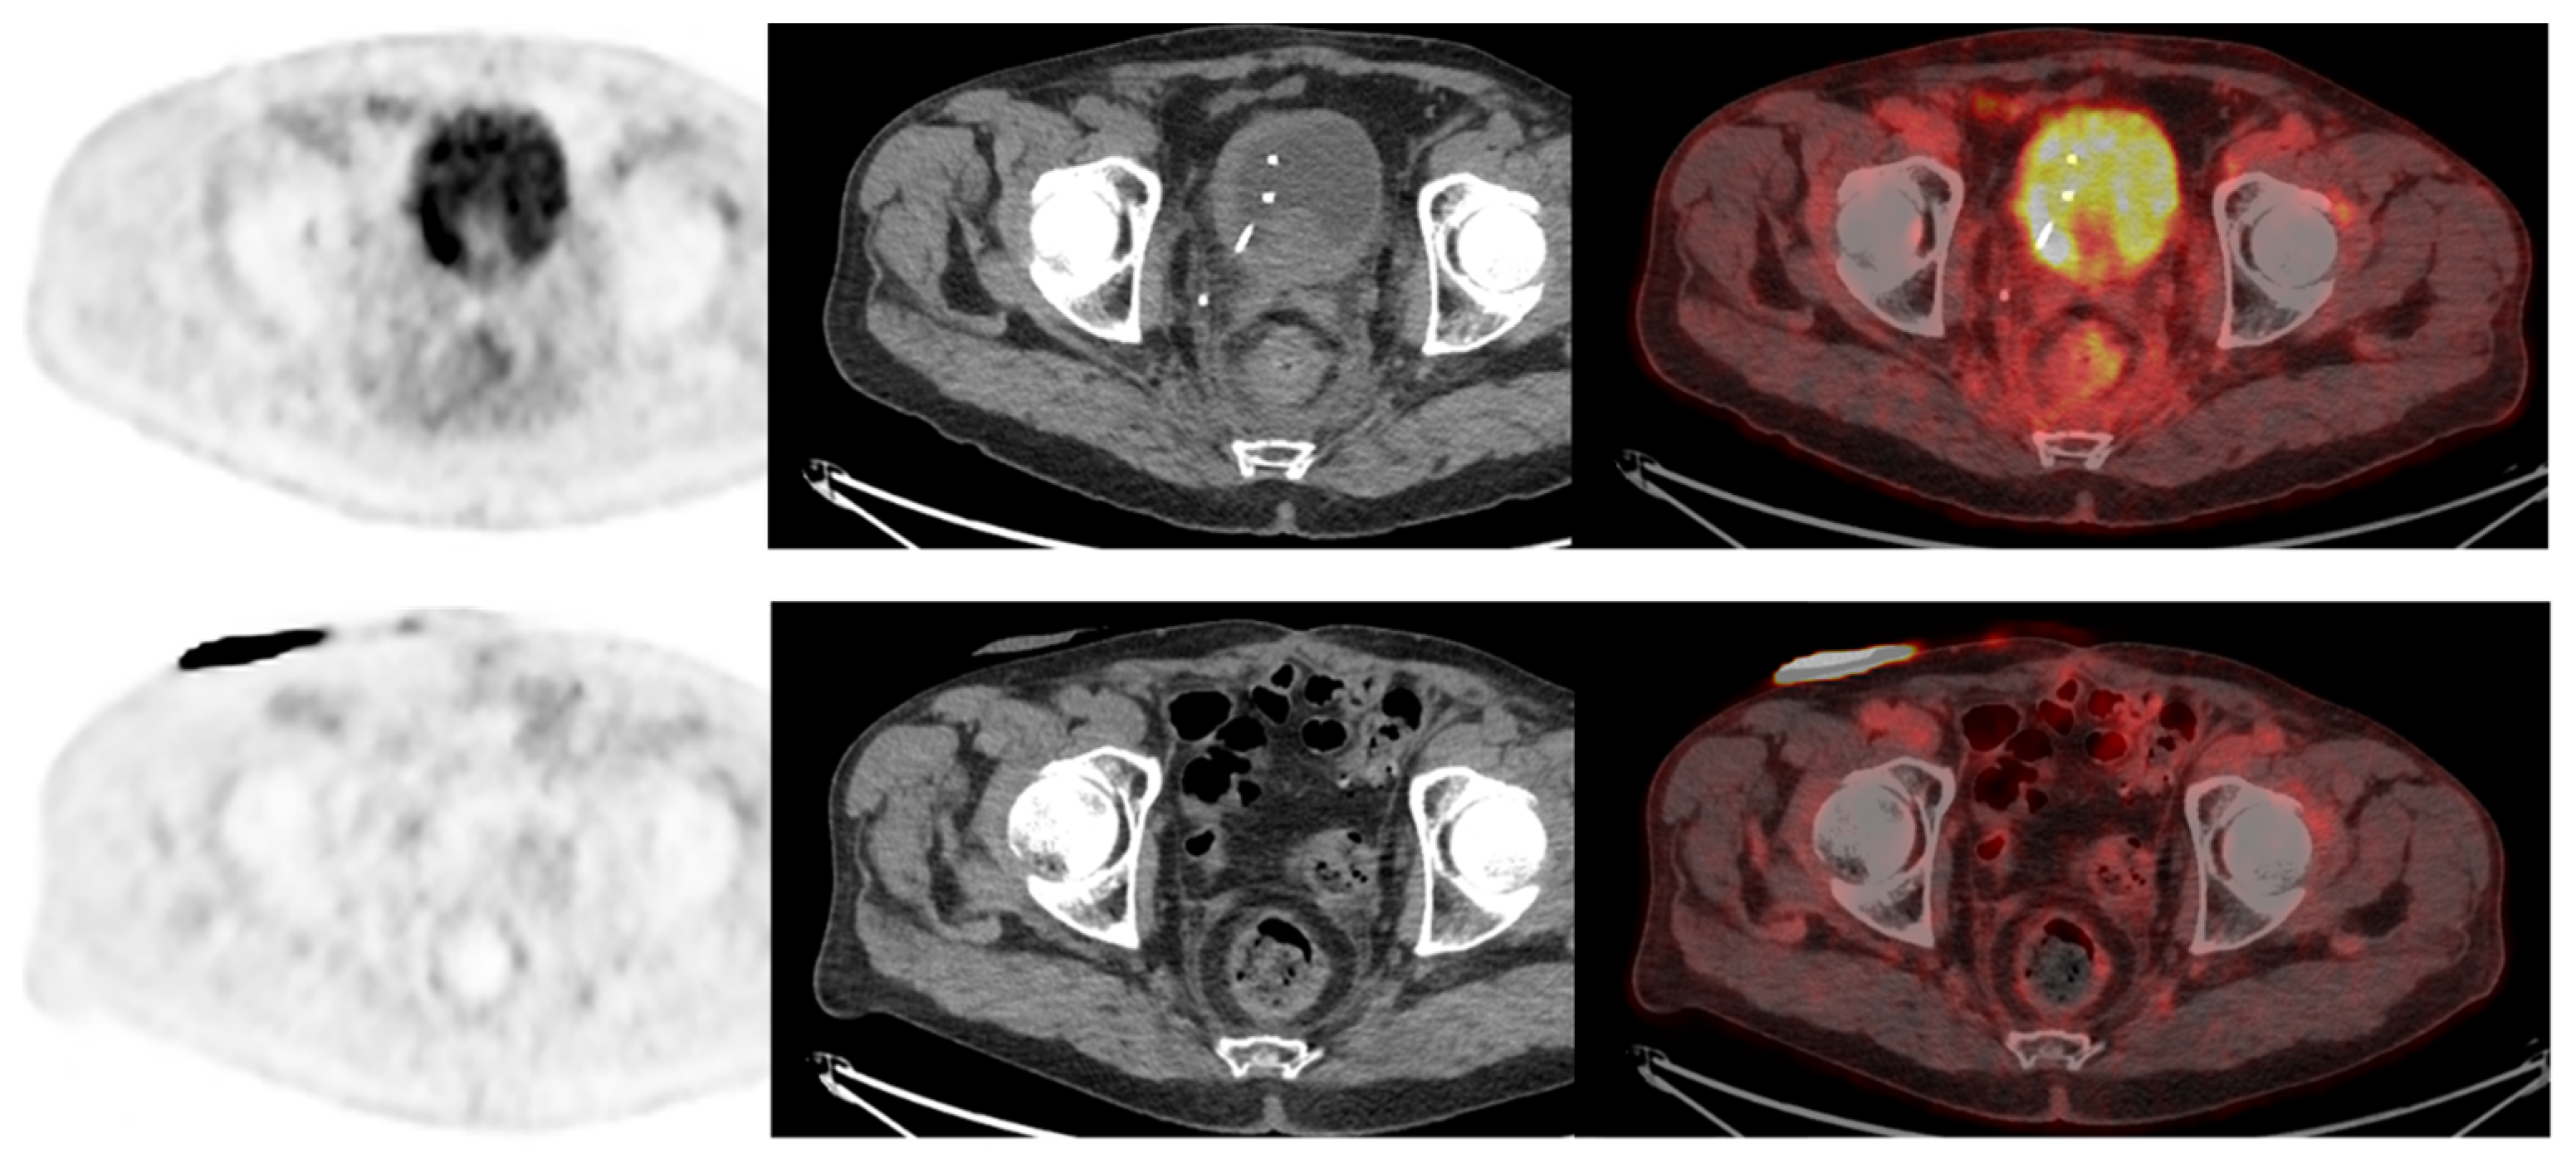

- Unterrainer, L.M.; Lindner, S.; Eismann, L.; Casuscelli, J.; Gildehaus, F.-J.; Bui, V.N.; Albert, N.L.; Holzgreve, A.; Beyer, L.; Todica, A.; et al. Feasibility of [68Ga]Ga-FAPI-46 PET/CT for detection of nodal and hematogenous spread in high-grade urothelial carcinoma. Eur. J. Nucl. Med. 2022, 49, 3571–3580. [Google Scholar] [CrossRef]

- Novruzov, E.; Dendl, K.; Ndlovu, H.; Choyke, P.L.; Dabir, M.; Beu, M.; Mehdi, E.; Guliyev, F.; Koerber, S.A.; Lawal, I.; et al. Head-to-head Intra-individual Comparison of [68Ga]-FAPI and [18F]-FDG PET/CT in Patients with Bladder Cancer. Mol. Imaging Biol. 2022, 24, 651–658. [Google Scholar] [CrossRef] [PubMed]